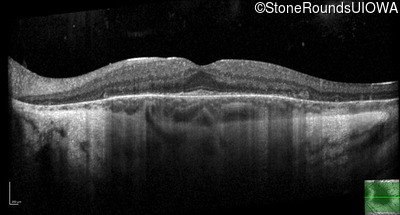

Optical Coherence Tomography - Left - 20/30 +1

Exemplar / OCT Stack

OCT Stack

Infrared Fundus Photograph - Right - 20/20 -3